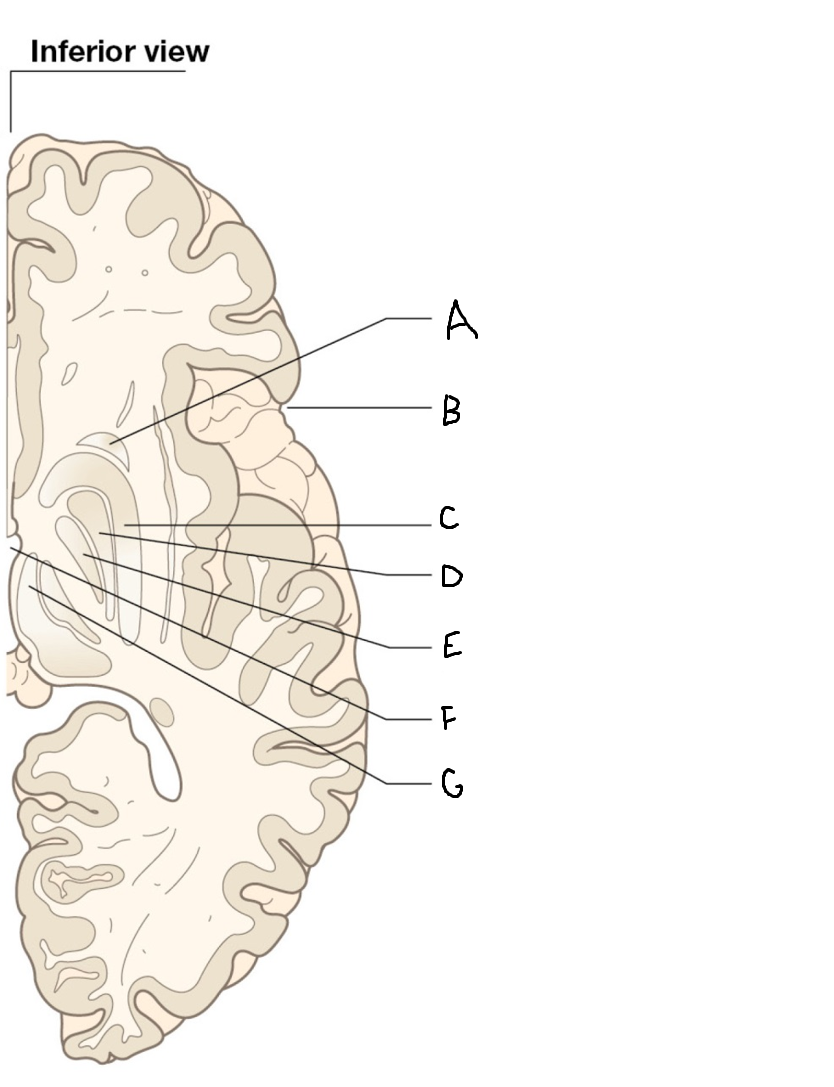

A

internal capsule (anterior limb)

B

caudate nucleus body

C

caudate nucleus head

D

putamen

E

caudate nucleus tail

F

thalamus

G

internal capsule (posterior limb)